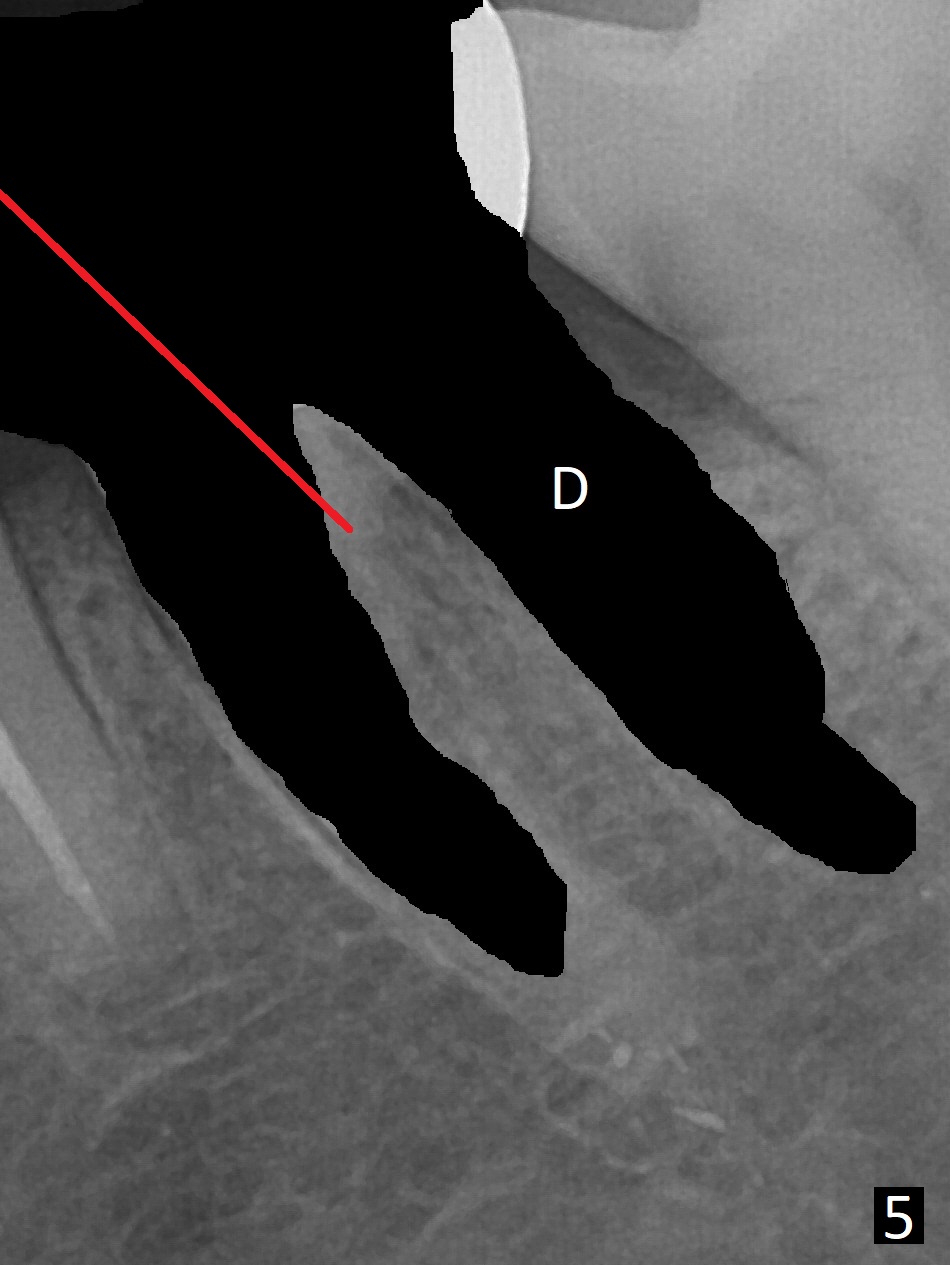

A 54-year-old man has distal (D) root fracture at #19 while the implant at #2 is osteointegrarting (Fig.1,2). Because of the large distal defect (Fig.3, after extraction), osteotomy (red line) will be initiated in the mesial socket (Fig.4, as distal as possible, with the coronal end in the middle of the socket) or the mesial slope of the septum (Fig.5) so that the implant (green) will be supported by the distally displaced septum (Fig.6 arrow). CT taken 8 months later confirms distal root fracture. A 6x11.5 mm or longer implant seems to be appropriate for the site (Fig.7). Three years later there is severe buccal swelling (Fig.8) with vertical mesial and distal root fractures (Fig.9). Although the buccal plate is lost, the septum remains (Fig.10 S), which will provide with blood supply to the bone graft (Fig.11), covered with Bioxclude and 6-month membrane and PSA suture. The bone density in the mesial and distal sockets is higher than that in the septum 8 months post cortical bone graft (Fig.12). In spite of bone graft, the buccolingual width reduces by almost 4 mm 8 months post extraction (Fig.3,4). In spite of bone graft, the buccolingual width reduces by almost 4 mm in 8 months post extraction (Fig.3,4). A 5x11.5 mm implant will be placed (Fig.15).